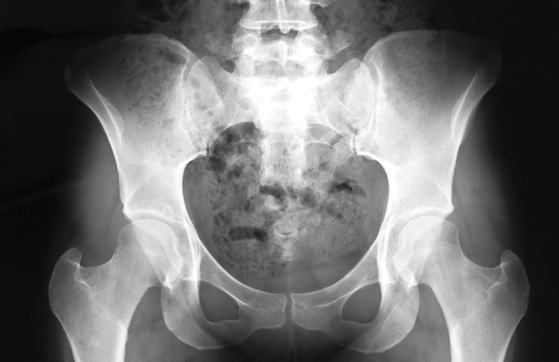

骨盤の写真をみてみましょう。

骨と骨の間の適切な「すきま」が見えますか?

この適切なすきまこそ、「骨盤のあそび」を作ってくれる基礎です。そして、この「骨盤のあそび」は、すきまがありすぎても、なさすぎてもボディメイクするには良くありません。現実にはすきまがありすぎという女性よりも、すきまが無さすぎで骨盤回りがガチガチに固まっている女性が以外に多いものです。